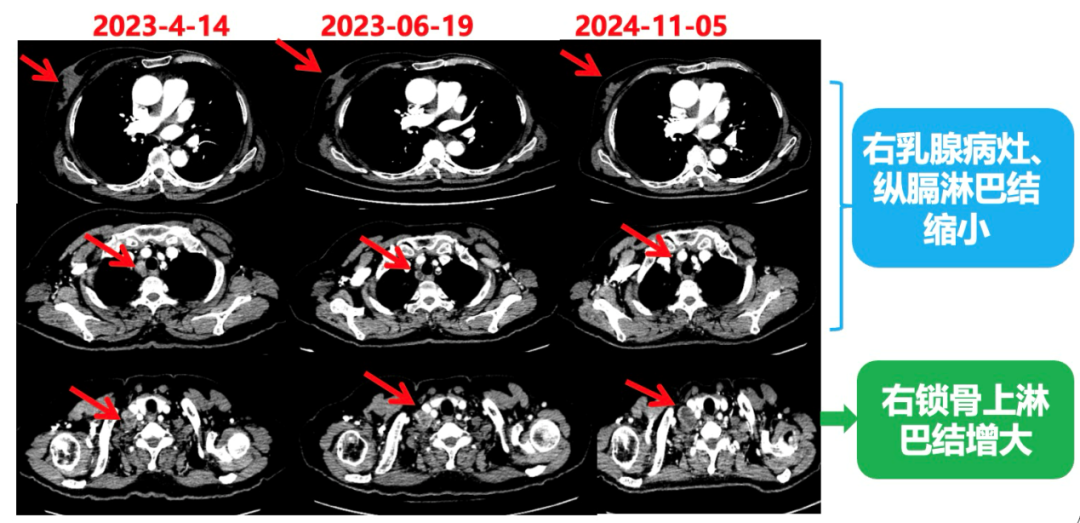

1.右乳外上象限乳腺癌病灶(22*16mm),对比2023-04-14 CT(26*24mm)较前缩小,FDG代谢活跃。右侧腋窝小淋巴结(5mm),较前稍缩小,代谢不活跃。右侧锁骨上区、上纵隔淋巴结转移瘤(24*18mm),现大小同前相仿,代谢活跃(SUV:6.7)。

患者已接受胃癌根治术,术后通过PET-CT对病灶情况进行了评估。目前患者采用哌柏西利联合氟维司群方案治疗,乳腺病灶已明显缩小,但锁骨上淋巴结、纵隔及肺门淋巴结未见缩小。为进一步为患者制定更精准的治疗方案,龚畅教授与曾银朵教授组织了第二次多学科联合会诊。

2024-11-5复查CT:右乳外上象限占位(11mm×9mm),较前明显缩小;上纵隔及右肺门多发淋巴结转移缩小;右锁骨上区淋巴结较前增大。余部位未见肿瘤转移及复发征象。

患者右锁骨上淋巴结较前增大,乳腺病灶明显缩小,针对是否需要进行锁骨上淋巴结及乳腺手术,龚畅教授和曾银朵教授又组织了第三次多学科会诊。